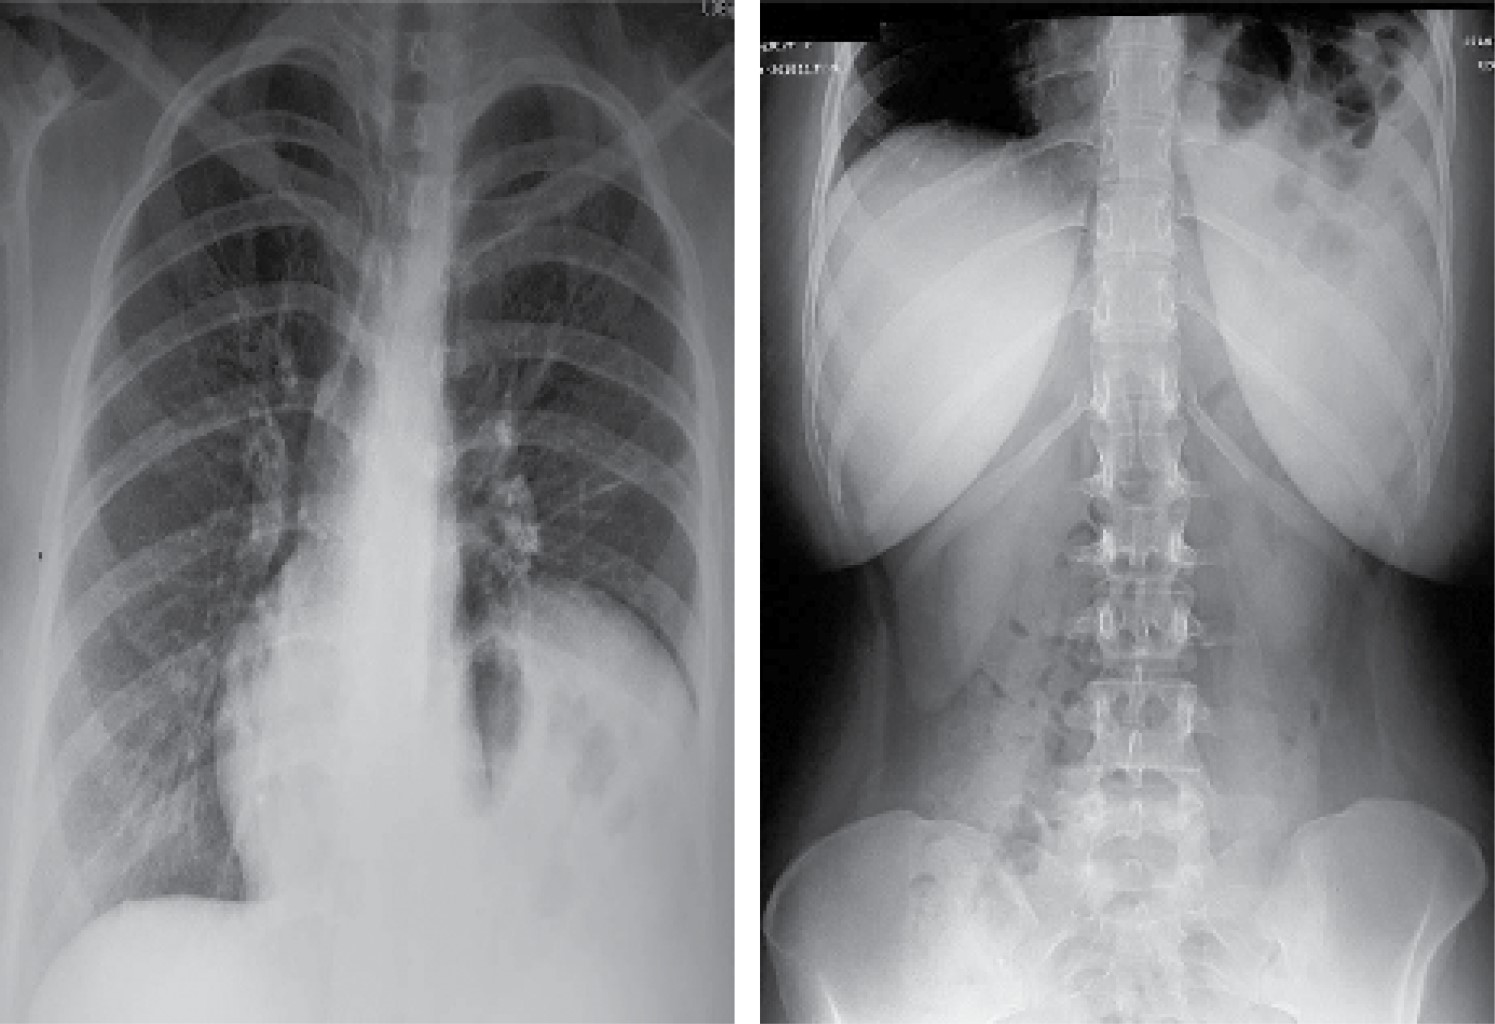

Radiografía de tórax a su ingreso con imagen radiopaca basal izquierda con niveles hidroaéreos (Figura 1), por lo que se solicita estudio tomográfico que confirma la presencia de una hernia diafragmática izquierda con colon, bazo, estómago e intestino delgado dentro de su contenido (Figura 2).

Figura 1